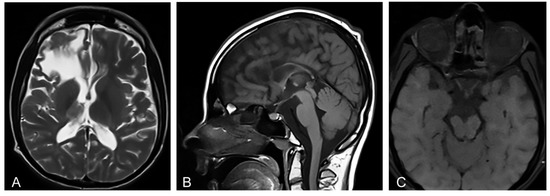

3.1. Imaging Findings